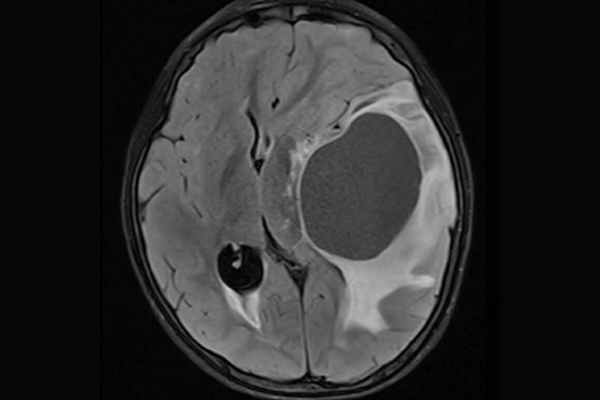

High-grade gliomas are a group of aggressive brain tumours and one of the deadliest tumours in children and young adults. In some children, the tumours are driven by mismatch repair deficiency (MMRD), which is characterized by hypermutation (a large and quickly accumulating number of mutations in tumour cells) and resistance to standard treatments such as chemotherapy and radiation.

priMMRD-2: The double agent

These tumours account for 19 per cent of the gliomas studied and have MMRD mutations without PPD or IDH1 gene alterations. For these patients, a single-agent immunotherapy is less effective, but adding a second agent may improve outcomes. The OPTIMISE trial, led by Dr. Daniel Morgenstern at SickKids, is using an adaptive trial design to target these specific genetic variations.